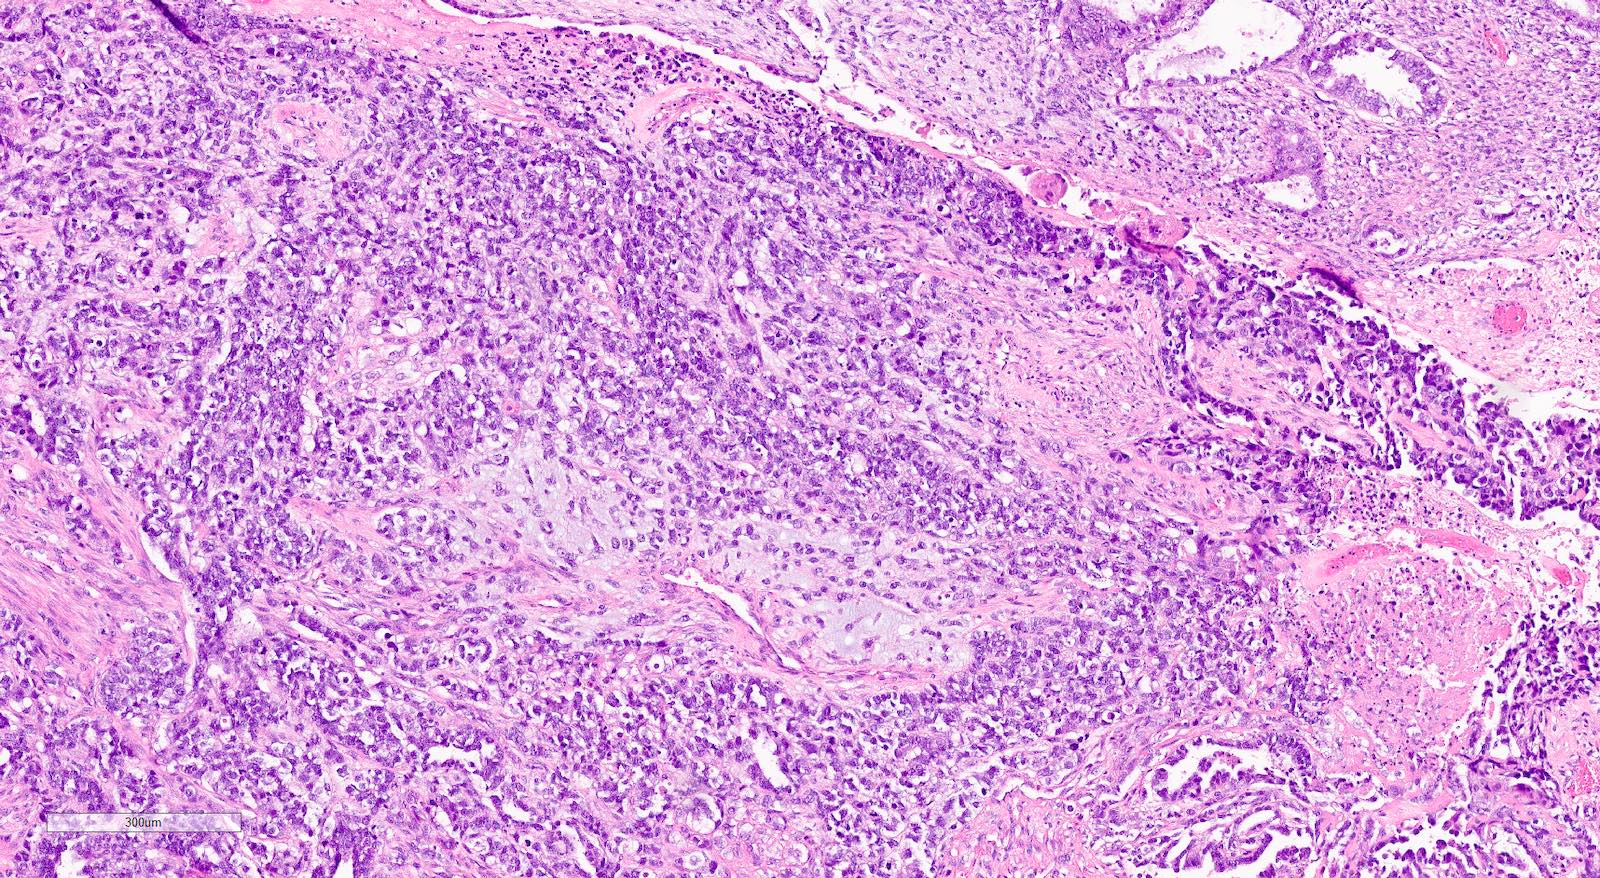

Microscopic (histologic) description

- Biphasic tumor with carcinomatous and sarcomatous elements, both high grade (Int J Gynecol Pathol 1990;9:1)

- Carcinomatous and sarcomatous components are juxtaposed

- Carcinomatous elements:

- Often high grade endometrioid or serous carcinoma, frequently admixed

- Hybrid morphology between endometrioid and serous carcinoma is frequent, as is undifferentiated carcinoma (Mod Pathol 2010;23:781)

- Sarcomatous elements:

- Often spindle and pleomorphic

- 50% contain heterologous elements (most commonly rhabdomyosarcoma and chondrosarcoma) (Am J Surg Pathol 2007;31:1653)

Microscopic (histologic) images